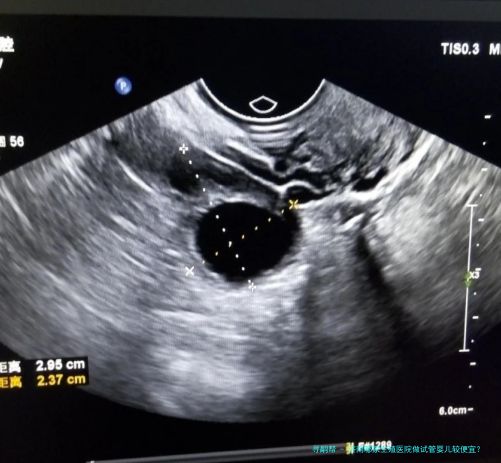

诊断费:对于试管婴儿技术,起首需要进行诊断,以认定病患是不是适合进行试管婴儿技术,病人的生殖系统肿瘤、妊娠合并症等情况,所以诊断费是必不可少量的。一般来说诊断费用约为一千元左右。检查费:检查费包括试管婴儿助孕技术评介、腹腔镜检查、辅助生殖技术检查等,一般情况下,检查费用约为2000元左右。药物费:在试管婴儿技术过程当中,需要适当的药物支持,多见的药物费用有激素费、人工受精费、着床技术费等,一般情况下,药物费用约为3000元左右。医疗费:医疗费主要包括试管婴儿技术手术费用及精子搜集费用等,正常情况下,医疗费用约为5000元左右。住院费:如果需要实行住院手术,依旧要支付住院费用,正常情况下,住院费用约为3000元左右。孕检费:试管婴儿技术完成后,须要定期进行孕检,以确定胎儿是否是生长正常,通常情况下,孕检费用约为2000元左右。

在济南生殖医院进行试管婴儿技术普通须要花费3万元左右。但实际费用还需要根据患者的实际情况而定,因而针对您的情况,建议您前往济南生殖医院进行具体咨询,以确定更准确的费用。